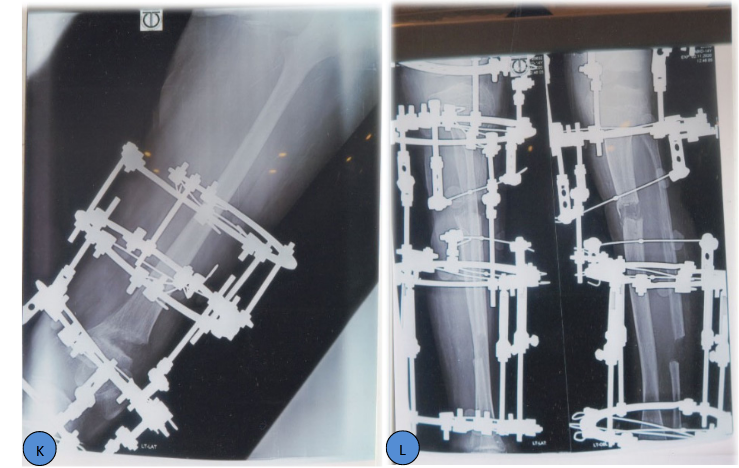

Post-traumatic femoral valgus and upper tibia valgus and procurvatum deformity with 10cm LLD were corrected with Ilizarov Technique. The lower femur deformity correction and deformity correction of upper tibia and lengthening were carried out simultaneously. This case demonstrates an approach to large complex post-traumatic deformity in the left knee region with puckering of the skin and bad scar.

Two steps of surgeries were calculated.

Everything must be done gradually. In Ilizarov technique gradual distraction is always preferred when amount of deformity is large and bone lengthening is necessary. Here the skin is very bad with bad scar and puckering is obvious.6,7

Figure 1 K-T